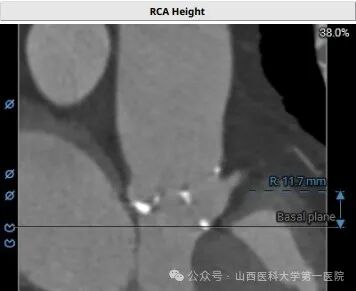

郭建军主任医师介绍,TAVI手术是一种微创心脏瓣膜置换手术,通过股动脉或心尖途径,将人工瓣膜植入以替换病变或异常的主动脉瓣膜。相较于传统开胸手术,TAVI手术对患者身体损伤小、术后恢复快、死亡率也大大降低,然而手术要求精细至毫米级,技术难度极高,必须在多学科专业团队协作下在专门杂交手术室内实施。该患者情况尤为复杂,主动脉及主动脉瓣钙化严重、左右冠脉开口位置低,手术风险极大,在郭建军主任医师团队的精湛技艺和全体参与人员的共同努力下,手术获得圆满成功。